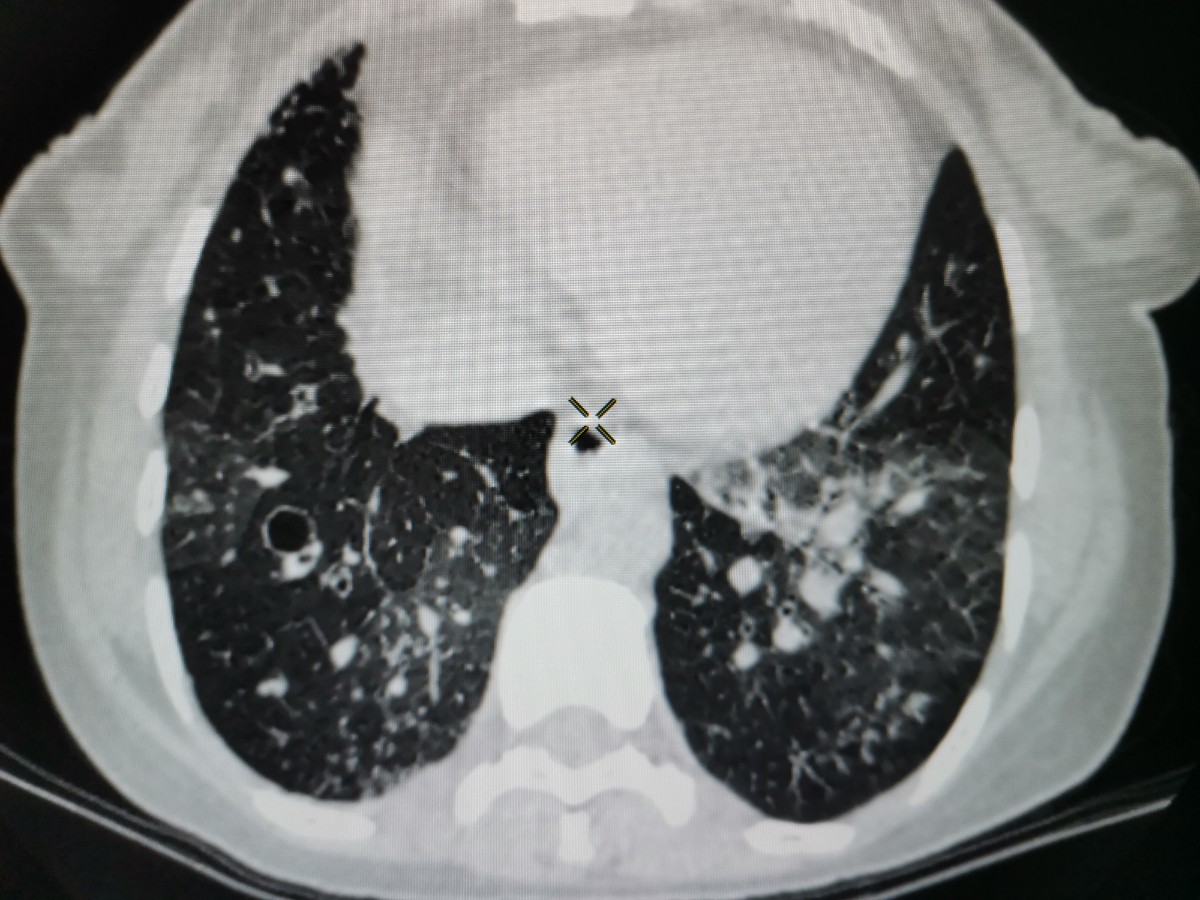

32岁女性,既往体弱,十几岁开始哮喘,既往检查不详,今日打新冠疫苗后出现昏迷,血象不高。CT多发支气管扩张报感染,较弥漫分布磨玻璃影,而且部分层面可见小叶间隔有膨胀、下坠改变,上肺胸膜下见少许结节,沿支气管血管束周围分布;老师们,这个病人如何诊断,如何解释肺部征象?